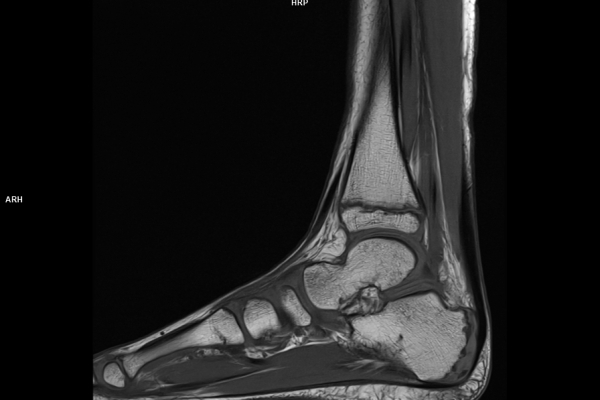

Detailbild MRT

Die MRT (Magnetresonanztomographie) arbeitet mit Magnetfeldern und Radiowellen und eignet sich besonders für Untersuchungen der Weichteile wie Gehirn, Muskeln oder Gelenke. Die CT (Computertomographie) nutzt Röntgenstrahlen und liefert schnelle, hochauflösende Bilder, insbesondere für Knochen, Lunge oder innere Organe. Die Wahl der jeweiligen Untersuchung richtet sich an das individuelle Krankheitsbild und wird bei der Überweisung festgelegt.